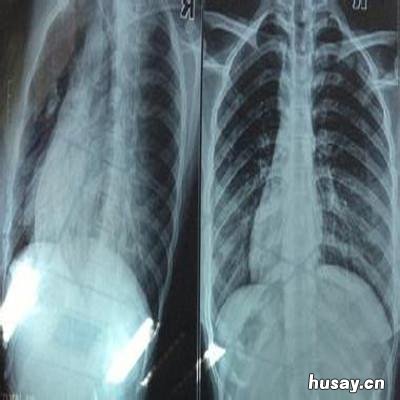

在生活中稍微的跌撞便能够引发人们出现肋骨骨折的情况,而肋骨骨折则会导致患者无法正常生活,为此,骨折患者就需要弄清楚肋骨骨折多久才能好的问题 。

【肋骨骨折多久能好 左侧肋骨骨折多久能好】肋骨骨折一般一个半月左右可以愈合 。肋骨骨折患者要保证休息、避免患处的受压、大声咳嗽、突然转身及弯腰等动作,以免加重症状或是引发并发症 。

其实,肋骨骨折多久能好的问题是与治疗的方法有关的,而目前常用的一种方式便是中医疗法,早期骨折用药7天左右疼痛可以基本减轻,肿也可以逐渐消退 , 全程用药大约30-40天左右可以基本恢复正常生活活动 。

骨折后如果不用中药治疗,单靠静养自身慢慢恢复,这样的治疗十分缓慢 。快则3个月痊愈,慢则6个月痊愈,不过也有些半年以上甚至一年都没有彻底痊愈的 。